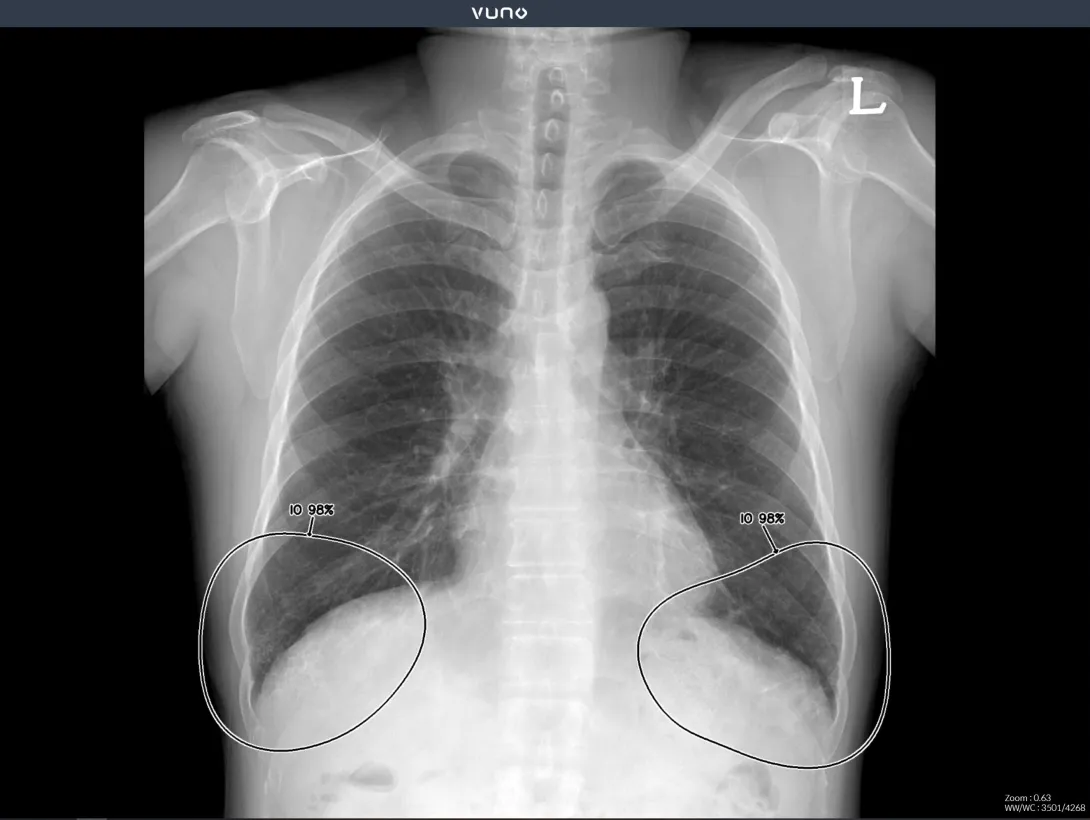

South Korean medical imaging firm VUNO has published a study showing that its Med-Chest X-Ray helps improves detection and localisation of major abnormal findings on chest radiographs, while reducing reading time. The study was published in the academic journal Radiology.

The study was conducted on three groups of people, each comprising assessors with varying experience levels – residents, board-certified radiologists, and thoracic radiologists. It compared the readings of chest radiographs from those who used the Med-Chest X-Ray against the readings of those who did not use the software.

It was shown that diagnostic accuracy across all performance, including per-lesion and per-image sensitivity, improved significantly. Reading time was also cut by an average of 50%.

According to a VUNO statement, the results of the study "reaffirmed that the solution is a useful diagnostic support tool for all clinicians regardless of their years of experience, not just for cases with a single lesion but also for those with multiple lesions and abnormal findings".

VUNO notes that past studies assessing the effects of similar solutions "may have biased the results" due to reading order or recall bias. To reduce such bias, the company’s study used a randomised crossover design with a washout period.